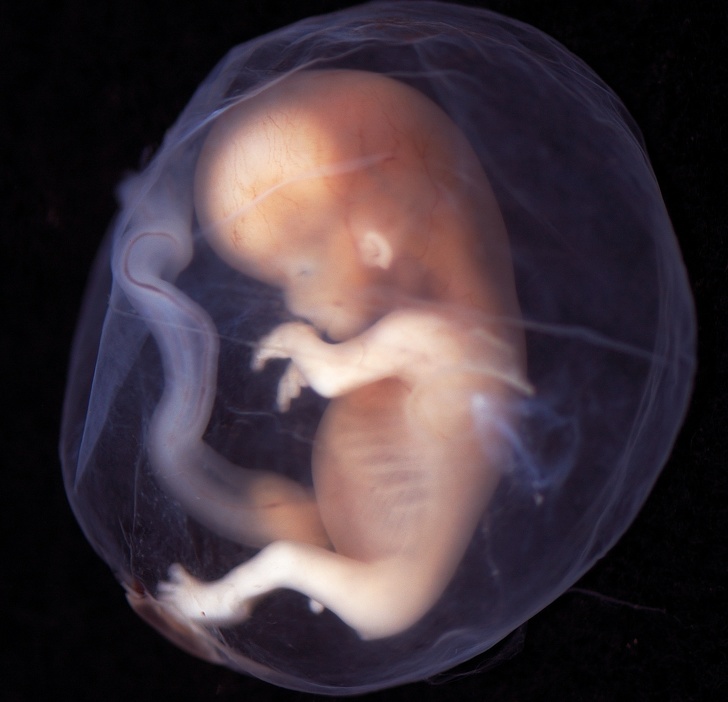

Дитина на 9-10-му тижні вагітності.

До цього часу малюк вже добре підріс — його вага становить 4 г, а зріст — 2-3 див. Незважаючи на крихітні розміри, мозок уже розділений на дві півкулі, а молочні зуби і смакові рецептори починають формуватися. У малюка зникає хвостик і перетинки між пальцями на руках, він починає плавати в навколоплідної рідини і ще більш активно ворушитися, хоча і так само непомітно для мами. Саме в цей час у дитини з'являються індивідуальні риси особи, а на голові починають рости волосся.